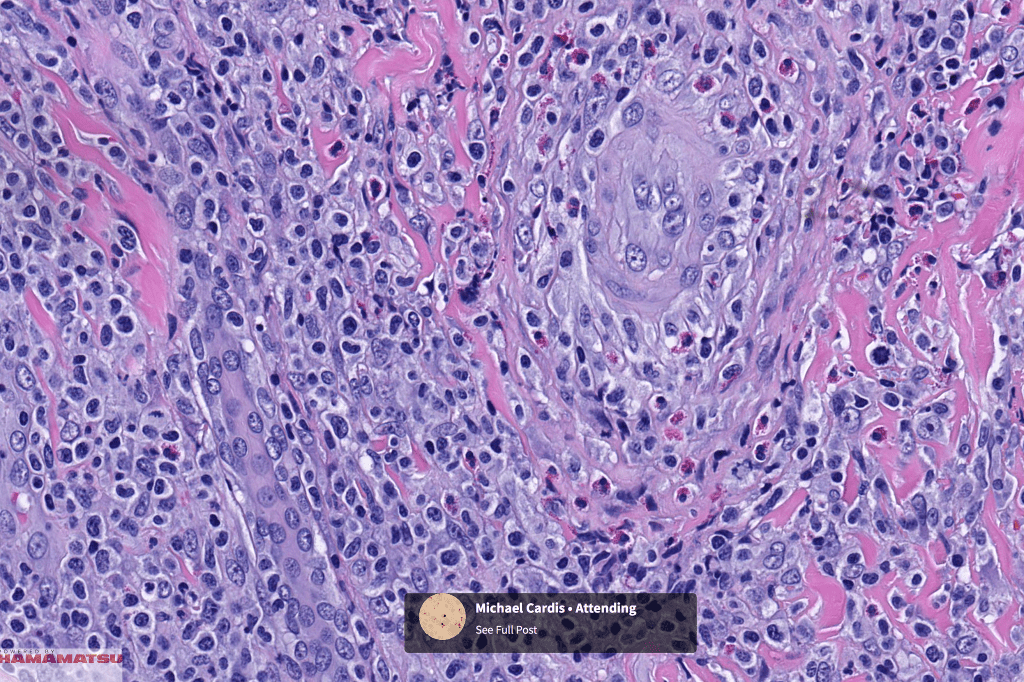

•Type A: 75-80%, wedge shaped infiltrate with base uppermost, large, anaplastic cells with abundant cytoplasm and vesicular nuclei containing prominent nucleoli, can resemble Reed-Sternberg cells, conspicuous mitoses & background infiltrate of lymphocytes, plasma cells, histiocytes, neutrophils & eosinophils

•Variable epidermal necrosis, epidermotropism, edema, hemorrhage & vasculitis/thrombosis